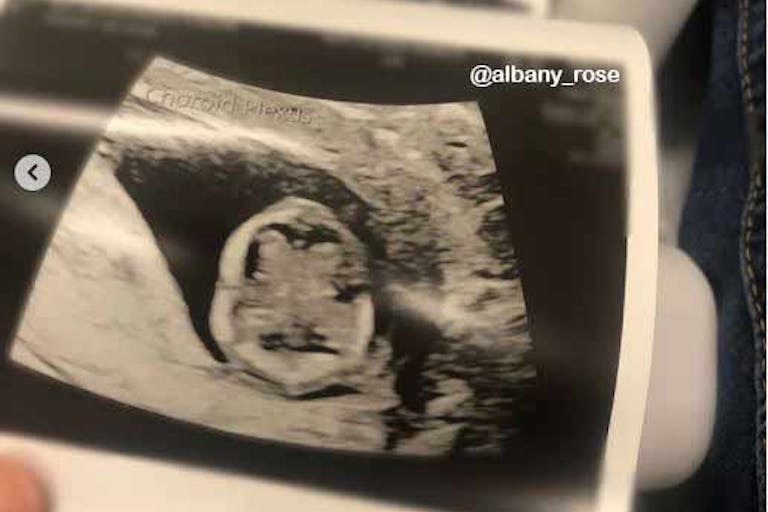

Pro-life activist shares remarkable scan of 12-week-old preborn baby’s brain

Pro-life activist Albany Rose recently shared a detailed ultrasound image of a friend’s 12-week-old preborn child. The image clearly shows the two hemispheres of the brain from the top — an ultrasound scan few will ever see.

“First and foremost, this baby is healthy and mama is so relieved there aren’t words,” said Rose. “This is a scan of the brain at 12 weeks. It just blew my mind! Because this is high risk, the scans were specific for the brain. You don’t generally get this on a standard [ultrasound].” According to the Endowment for Human Development, the corpus callosum of the preborn child — connecting the left and right hemispheres of the brain — forms between 11 and 12 weeks.